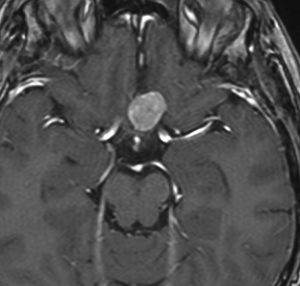

小児期の低線量照射で生じた多発性髄膜腫

5歳の時に白血病,化学療法と低線量頭蓋照射で治りました。ちゃんと就職して重機の運転をしていましたが,30歳,左足の痙攣で発症しました。多発性髄膜腫が発生していました。摘出する必要があるものです。グレード1の良性の髄膜腫です。